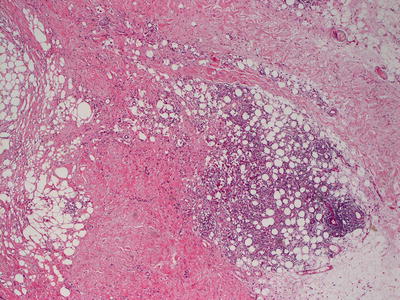

9.3.2 Histology

Biopsy of subcutaneous fat necrosis of the newborn demonstrates a lobular panniculitis [19] (Fig. 9.5). There is a diffuse, brisk mixed inflammatory infiltrate within fat lobules. Necrosis of adipocytes results in crystal formation and small granulomas surrounding the degenerating cells [20] (Figs. 9.6 and 9.7). Crystals are needle-shaped, and can be present within degenerating adipocytes and histiocytes [21, 22]. Eosinophilic granules , a manifestation of degenerating eosinophils within the surrounding infiltrate, have been observed in some cases [23–25]. Dystrophic calcification is seen in late cases [20, 26, 27]. Radially oriented needle-like crystals are helpful in establishing the diagnosis on fine needle aspiration cytology [28, 29].

Fig. 9.5

Subcutaneous fat necrosis of the newborn is a lobular panniculitis that is characterized by a predominantly histiocytic response